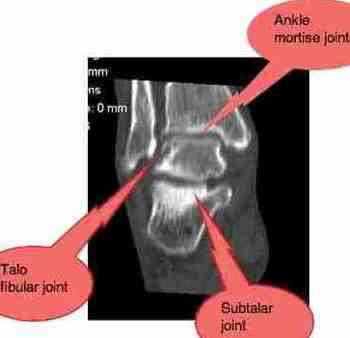

Diagram of ankle anatomy

The sharp pain within the ankle joint is more complicated; it may just be a chronic subluxation in the ankle mortice or subtalar joints, both of which cause sharp stabs of pain. That responds well to chiropractic adjustments.

3. Subluxate bones in the ankle, usually the mortise or subtalar joints.